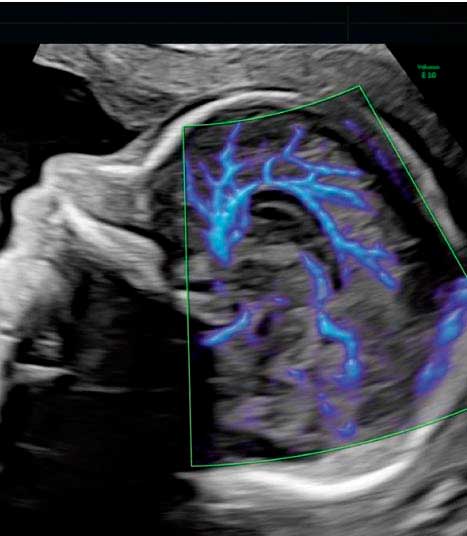

Examen que evalúa detalladamente el sistema nervioso fetal considerando que las malformaciones del sistema nervioso central son entidades de alta frecuencia (hasta 1 de cada 100 recién nacidos). La presencia de una malformación en estas estructuras puede tener importantes implicaciones funcionales y del desarrollo tras el nacimiento.

INCLUYE:

– Ecografía en HD Live Resolution (5D/7D).

– Estudio Doppler.

– Informe e imágenes impresas en b/n.

– Una foto postal a color.

– Video e Imagénes de la ecografía en MP4 y JPG enviados a su correo electrónico via nuestra cuenta corporativa en WeTransfer.

– Estacionamiento incluido.

– Explicación de los hallazgos ecográficos.

Examen que evalúa detalladamente el sistema nervioso fetal considerando que las malformaciones del sistema nervioso central son entidades de alta frecuencia (hasta 1 de cada 100 recién nacidos). La presencia de una malformación en estas estructuras puede tener importantes implicaciones funcionales y del desarrollo tras el nacimiento.

INCLUYE:

– Ecografía en HD Live Resolution (5D/7D).

– Estudio Doppler.

– Informe e imágenes impresas en b/n.

– Una foto postal a color.

– Video e Imagénes de la ecografía en MP4 y JPG enviados a su correo electrónico via nuestra cuenta corporativa en WeTransfer.

– Estacionamiento incluido.

– Explicación de los hallazgos ecográficos.

Dr. Enrique Gil G.